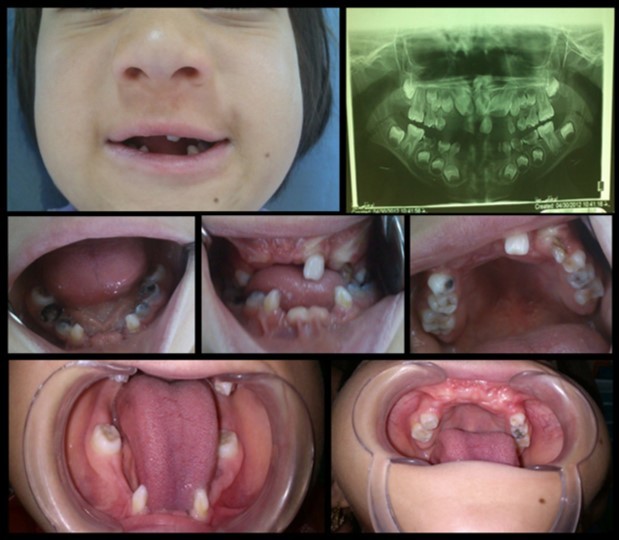

The mandibular and maxillary incisors were absent (excluding upper left lateral maxillary incisor which was loose) mandibular deciduous molars, right maxillary first deciduous molar and left deciduous maxillary canine had severe decay and the right maxillary permanent canines were erupting. Multiple frenulum and attaching labial mucosa to alveolar mucosa were also observed (Figure 2).

In Radiographic examination of tooth, maxillary incisor tooth germs were absent and all of the four “second permanent molars” were un-erupted and root of primary mandibular canines have severe mesial curve (Figure 2).

Figure 2.Intra oral photographs and panoramic radiograph: anodontia of mandibular and maxillary incisors, absence of mucobuccal fold in maxillary and mandibular anterior region, congenital absence of the incisors, conical shaped teeth and multiple frenula.